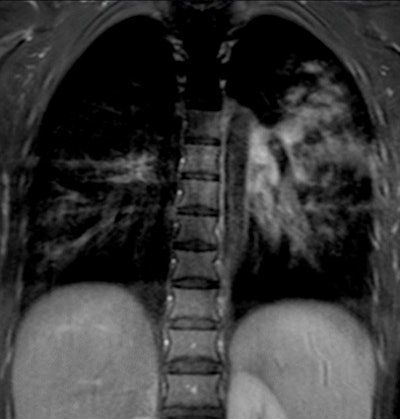

| A 13-year-old girl with pneumonia caused by Mycoplasma pneumoniae. Chest x-ray (above) and a contrast-enhanced 1.5-tesla coronal image (below). The MR image shows patchy parenchymal changes in both lungs. Images courtesy of the Department of Radiology, Turku University Hospital. |

![]() |